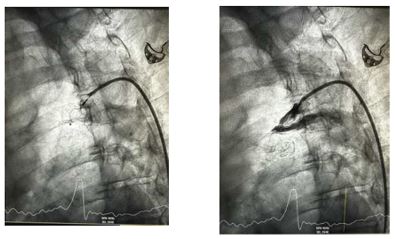

Στο Aιμοδυναμικό εργαστήριο της Β' Πανεπιστημιακής Καρδιολογικής Κλινικής στο Ιπποκράτειο Νοσοκομείο Θεσσαλονίκης πραγματοποιήθηκε για πρώτη φορά και με απόλυτη επιτυχία επέμβαση Σύγκλεισης Ανοικτού Βοτάλειου Πόρου. Η επέμβαση έγινε σε ενήλικα ασθενή με προσπέλαση από την αορτική πλευρά της επικοινωνίας και στη συνέχεια επιτυχή τοποθέτηση της συσκευής όπως επιβεβαιώνεται και αγγειογραφικά στις παρακάτω εικόνες.

Ακτινοσκοπικές λήψεις από την τοποθέτηση της συσκευής σύγκλεισης του Βοτάλειου Πόρου και η επιβεβαίωση της πλήρους σύγκλεισης μετά από χορήγηση σκιαστικού.